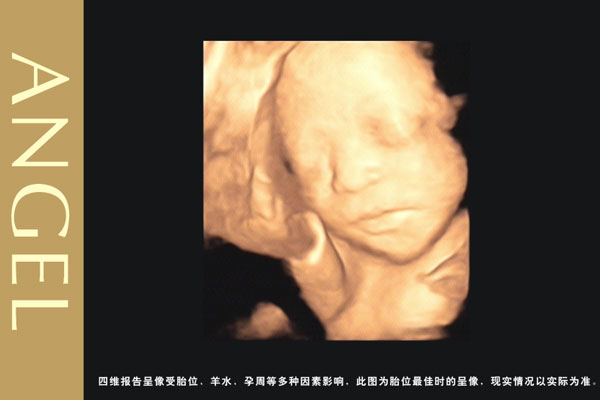

四维彩超和大排畸的区别 很多孕妈妈都会将四维彩超和大排畸之间傻傻分不清,其实大排畸形就是三维,那么,四维彩超和大排畸的区别是?

四维彩超和三维彩超有区别吗?三维彩超和四维彩超的区别就在于在一个“时间维”,也就是说,三维彩超是图片,四维彩超是录像,可以让孕妈妈看到胎儿一连串的动作。

四维彩超是动态的,三维彩超是静态的,所以四维看起来会更清楚明晰,三维彩超只能是某个时间点上的照片,四维彩超的就可以做成DV那样连续的,可以刻录光盘。三维彩超和高清四维彩超一样的有排畸的作用,高清四维彩超更加准确。